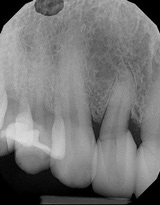

(2.) Pretreatment radiograph of tooth No. 7 showing widened periodontal ligament, dens in dente, dilacerations, and angular bone loss.

Figure 2

A 45-year-old female patient was referred to our office for the treatment of bleeding gums and sensitivity associated with tooth No. 7. Clinical and radiographic evaluations revealed highly inflamed tissues, easily provoked bleeding, and edematous palatal gingival tissue supporting tooth No. 7 (Figure 1 and Figure 2). Crowding, a widened periodontal ligament, dens in dente, deep probing depths, bleeding on probing, dilacerations, missing papilla, and angular bone loss were also observed, indicating that tooth No. 7 had a poor prognosis. The groove began at the cingulum and formed a deep fold of enamel that extended to the coronal third of the root. This radicular groove disrupted normal periodontal attachment and caused a self-sustaining, progressive localized periodontal pocket to form. The groove also presented a potential pathway for bacterial penetration into deeper parts of the root, which could lead to endodontic involvement if left untreated.6

(7.) A 3-year, posttreatment radiograph showing a significant improvement in the angular bone loss on the mesial aspect of tooth No. 7.

Figure 7